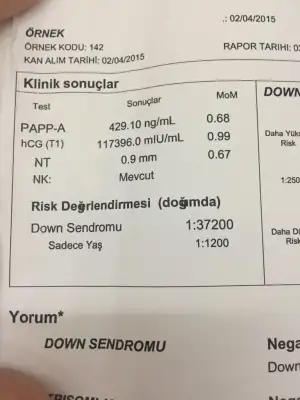

aynen öyle detaylida hicbir down sendromu belirtisine rastlamadim dedi doktorumda.Ben bugün gittim ikili test için kan verdim, foktor usg baktı cinsiyeti kesin olarak 20. Haftada söylecekmi

Canım ikili test sonucu için hiç üzülme, oranı yüksek çıkıp sağlıklı bebekleri olan o kadar çok insan var ki. Nifty testi yaptır sonuç ikili teste göre daha güvenilirdir.

Benim dpktorum şuan herşey çok güzel gifiyor, inşallah böyle devam eder. İkili test sonucu çıkınca da konuşuruz ama çok doğru sonuç vermiyor sanırım ki amniyosentez yaptırabiliriz istersen dedi.